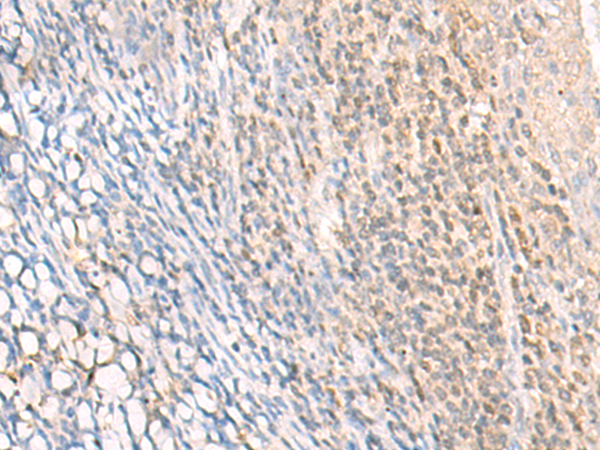

ELISA, IHC |

IHC positive control: |

Human cervical cancer and Human tonsil |

IHC Recommend dilution: |

30-150 |